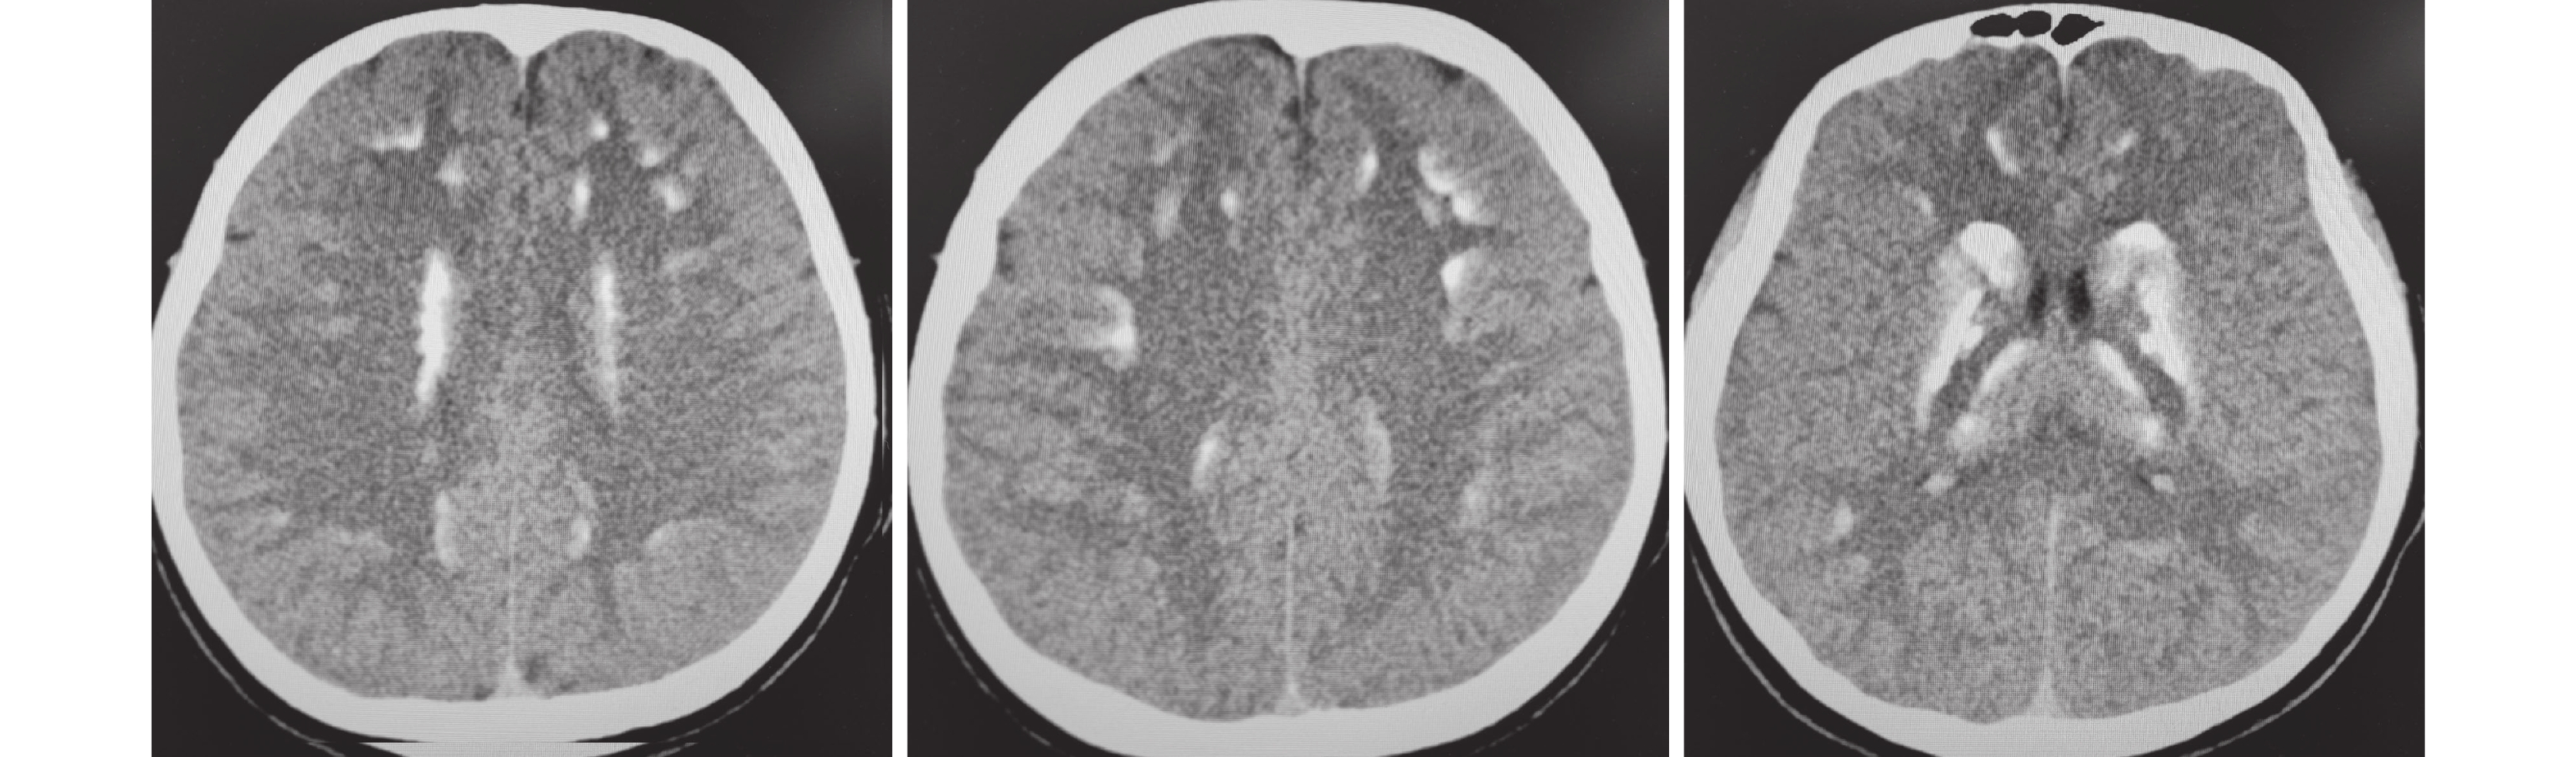

影像學檢查:入院心電圖正常。甲狀旁腺彩超未見異常。心臟彩超未見異常。全身骨代謝顯像未見異常。頭部計算機斷層掃描(Computed Tomography, CT)提示腦實質內多發對稱性鈣化(圖1)。